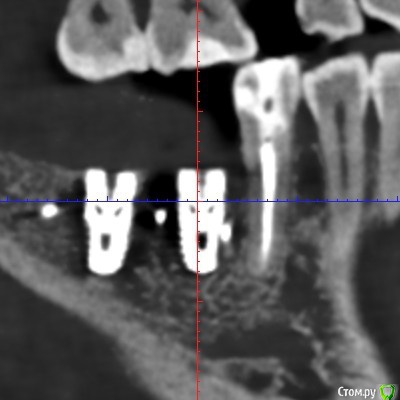

Irina_S Опубликовано 6 января, 2018 Поделиться Опубликовано 6 января, 2018 Здравствуйте, уважаемые спеицалисты! С наступившим вас Новым годом!!! В конце августа были установлены три имплантата Xive - 36, 46, 47. Одновременно с установкой выпиливалась кость и прикручивалась винтиками в те места, где по мнению хирурга её не хватало. В середине октября сквозь десну с язычной стороны стали просматриваться верхушки имплантатов 36 и 46. Во время периодических осмотров врач говорил, что всё в порядке.В декабре пришло время установки формирователей десны. Установивший имплантаты хирург стал работать в другой клинике. Он пригласил на осмотр, сказал, что надо будет добавить десну в области 36 и 46, взяв кусочки с нёба, а с самими имплантатами всё хорошо, можно одновременно с пластикой десны ставить формирователи и через 2-3 недели отправляться к ортопеду.Следуя логике сохранения гарантии на установку имплантатов, которую даёт не врач, а клиника, я пошла к другому хирургу в ту клинику, где устанавливались имплантаты. Он посмотрел на выступающие верзушки имплантатов, причём 36 успел к этому времени уже прорвать десну. Посмотрел КТ и сказал, что предварительно видит проблемы и помимо пластики десны может понадобиться переустановка имплантатов. Самый проблемный, по его мнению, 46, а 36 - под вопросом. Сказал, что окончательное решение можно будет принять только после разрезания десны, чтобы увидеть фактическую ситуацию. Причём переустановка - по гарантии, и она будет делаться сразу - выкручивается старый имплантат и ставится новый, тоньше (3,8мм вместо 4,5мм) и длиннее. Соответственно, в этом случае снова ждать 3-4 месяца, и только после этого ставить формирователи. Присутствовавший на консультации ортопед был полностью с ним согласен и сказал, что на имплантаты в таком состоянии, как он их видит на КТ, он коронки ставить не будет. Аргументировалось тем, что кости в принципе достаточно, но имплантаты надо было устанавливать глубже, а так, как сейчас, они протянут максимум 3-4 года, а потом расшатаются и выпадут. Клиника даёт гарантию 10 лет, поэтому они считают, что нужно хорошо установить изначально.На месяц раньше ставились имплантаты в верхнюю челюсть, с ними всё хорошо. Но, рассматривая проекции КТ, я вижу обширные тёмные области в районе всех имплантатов как дефект засветки при формировании КТ. В связи с чем вопрос: может ли картина на КТ с отсутствием видимой костной ткани происходить из-за самого оборудования, на котором делается КТ, и не совсем соответствовать действительности? Иначе, есть ли шанс, что при вскрытии десны окажется, что с расположением импллантатов всё в порядке (как и уверяет "сбежавший" их этой клиники хирург), а альтернативное мнение связано в некотором роде с желанием опозорить уволившегося сотрудника и удержать пациента у себя, ведь потом предстоит большая ортопедическая работа? И ещё один вопрос: чего мог категорически не принимать ортопед, говоря, что в подобных случаях он всегда отправляет к хирургу, если заведомо было известно, что недостающая десна в любом случае будет наращиваться?С имплантатом 47 ситуация, вроде бы, не такая критическая. Это на самом деле так? Ссылка на комментарий

колесников Опубликовано 6 января, 2018 Поделиться Опубликовано 6 января, 2018 Сколько врачей,столько и клинических подходов. Я бы переустановил нижние импланты заменив ксайв на Штрауман тл, плюс увеличил объём мягких тканей по гребню.Это ,как говорится ,обойтись малой кровью с благоприятным прогнозом. Если оставлять этот ксайв,то только пластики десны не достаточно,придётся перекрывать их костным материалом с мембраной и позднее Увеличить объём мягких тканей. Все бы ничего,но меня смущает язычное положение платформ имплантов и их уровень относительно соседних зубов. Это лично моё мнение,оно может отличаться от мнений коллег. Ссылка на комментарий

колесников Опубликовано 7 января, 2018 Поделиться Опубликовано 7 января, 2018 Не совсем так. Была совмещена костная пластика и имплантация,объема кости в итоге оказалось меньше чем планировалось получить. Ксайв хороший имплант,но должен быть окружён и погружён в достаточный объём костной ткани (тоже самое могло произойти и анкилос). Обычно этот момент обговариваемся заранее,что если кости будет в итоге мало,добавится ещё. Ваш хирург ушёл из клиники и новая команда решила пойти по более простому пути-переустановить имплант. Случай вполне распространённый. От вас не отказались,действуют гарантийные обязательства,имплант анкилос очень благодарная система. Рекомендую применить цифровое планирование и хирургический шаблон. Если на этапе планирования вам все станет понятно и понравится предполагаемый результатах-отбросьте сомнения. Ссылка на комментарий